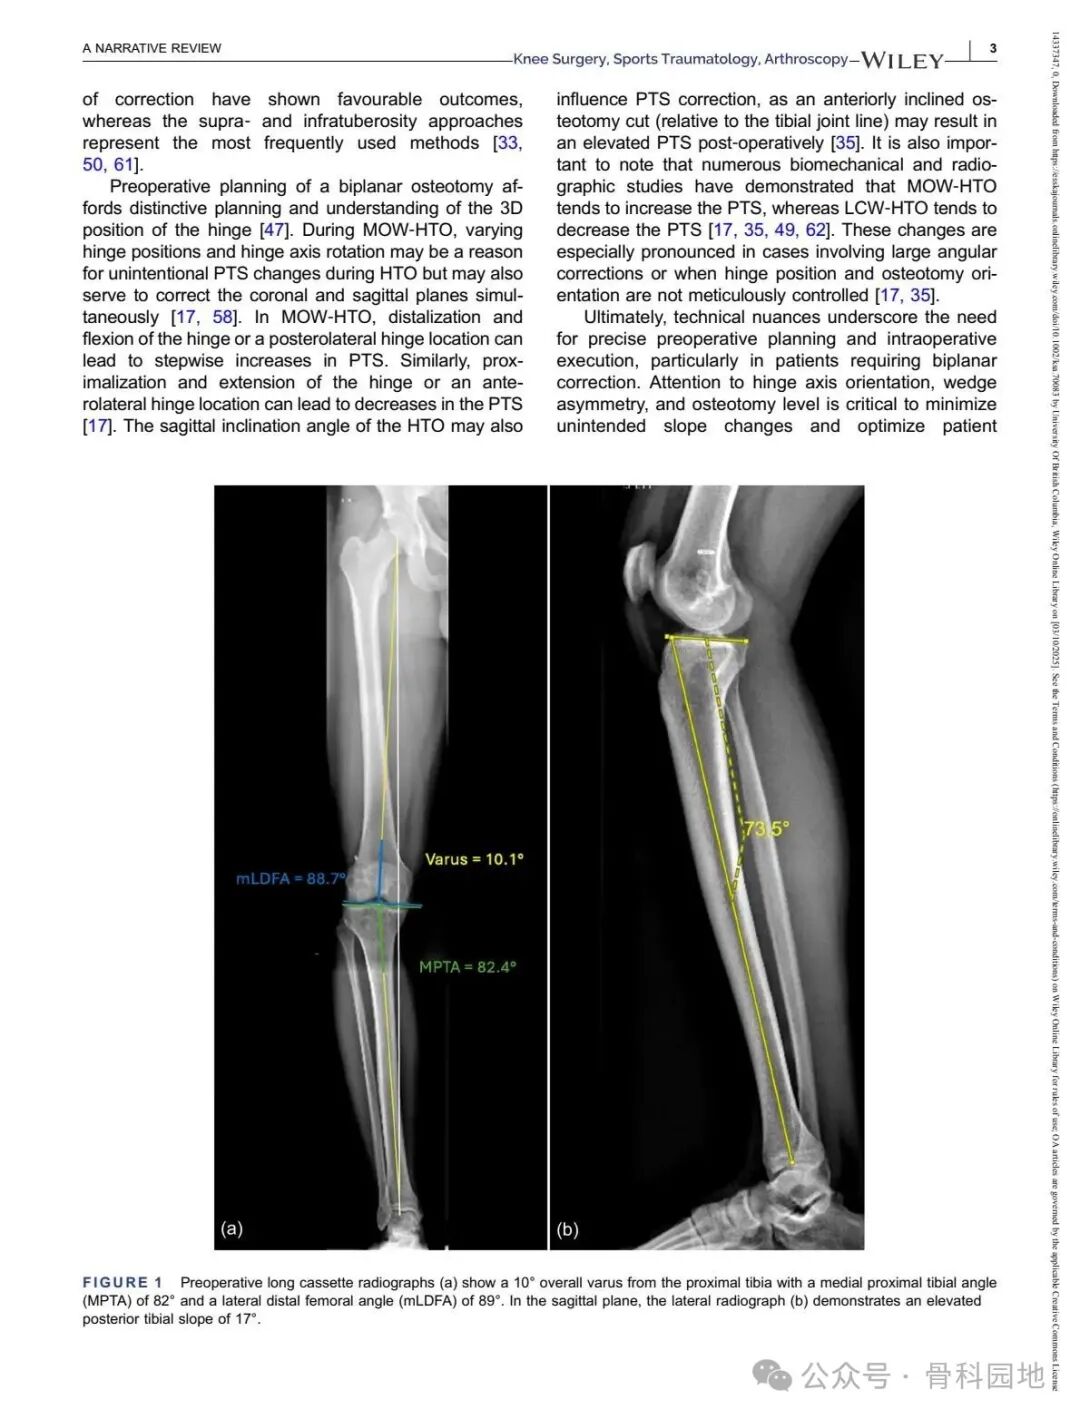

Although conventional high tibial osteotomy (HTO) primarily addresses coronal plane malalignment, the importance of sagittal plane alignment—specifically the posterior tibial slope (PTS)—cannot be overlooked in the setting of cruciate ligament insufficiency. Combined coronal and sagittal plane deformities are relatively rare and present unique surgical challenges. This narrative review summarizes the available literature and presents technical tips for managing complex biplanar deformities through a case‑based discussion of different techniques.